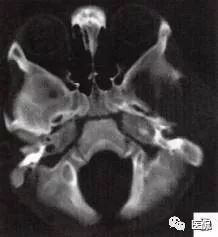

颅脑CT示:图A〜D,CT平扫示左侧额骨、蝶骨见溶骨性骨质缺损,边界清晰,周围无硬化边,伴有软组织肿块向脑外生长,边缘光滑,脑内无明显侵犯;

图E、F,横、 矢状位CT增强示软组织肿块轻度均匀强化,两病灶间亦见强化软组织影;